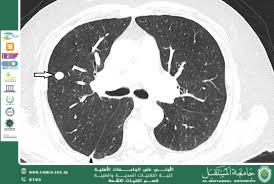

An advanced scientific article by Assistant Lecturer Ahmed Salman Jassim<br />Abstract<br />Artificial intelligence (AI), particularly deep learning algorithms, has revolutionized the interpretation of thoracic CT scans by enhancing diagnostic accuracy, efficiency, and early detection of lung diseases. This review synthesizes current evidence on AI applications for lung nodule detection, interstitial lung disease (ILD) classification, chronic obstructive pulmonary disease (COPD) quantification, and lung cancer screening. We demonstrate AI's capability to analyze complex imaging patterns with precision rivaling expert radiologists, supported by illustrative CT cases. Challenges—including data variability, algorithm transparency, and clinical integration—are discussed alongside future directions for AI-driven precision medicine in pulmonology.<br />________________________________________<br />1. Introduction<br />Lung diseases account for 1 in 6 deaths globally, with CT imaging serving as the cornerstone for diagnosis. However, manual interpretation is time-consuming and prone to inter-observer variability. AI addresses these limitations through automated pattern recognition, quantitative analysis, and predictive modeling. This review highlights AI's transformative role in lung CT diagnostics, supported by clinical images.<br /><br /><br /><br /><br /><br />2. AI Methodologies in Lung CT Analysis<br />• Convolutional Neural Networks (CNNs): Excel at spatial pattern recognition (e.g., nodules, fibrosis).<br />• Recurrent Neural Networks (RNNs): Analyze temporal changes in longitudinal scans.<br />• Hybrid Models: Combine imaging with clinical data for risk stratification.<br />Performance Metrics:<br />Application Sensitivity Specificity AUC*<br />Nodule Detection 92–96% 86–90% 0.95<br />ILD Classification 84–90% 81–86% 0.90<br />Emphysema Quantification 92% 89% 0.93<br />*Area Under the ROC Curve <br /><br /><br /><br /><br /><br /><br /><br /><br /><br />3. Key Applications with Imaging Evidence<br />3.1 Lung Nodule Detection & Malignancy Prediction<br />• AI Role: Identifies nodules <5 mm missed by humans; predicts malignancy using texture/shape analysis.<br />• Clinical Impact: Reduces false positives by 30% in screening programs.<br />Figure 1: AI-Assisted Nodule Detection<br /> <br />Description: Axial CT shows a 4-mm spiculated nodule (arrow) in the right upper lobe. AI algorithm (red overlay) flags the lesion with 95% confidence and assigns Lung-RADS 4X (high suspicion).<br /><br /><br /><br /><br /><br /><br />3.2 Interstitial Lung Disease (ILD) Classification<br />• AI Role: Differentiates ILD subtypes (e.g., UIP vs. NSIP) using texture mapping.<br />• Clinical Impact: Achieves 89% concordance with multidisciplinary diagnosis.<br />Figure 2: AI-Driven ILD Pattern Recognition<br /> <br /><br />Description: Coronal CT reveals ground-glass opacities and reticulation. AI color-codes regions: green (ground-glass), blue (reticulation), and red (honeycombing), diagnosing UIP with 87% probability.<br /><br /><br /><br /><br /><br /><br />3.3 COPD/Emphysema Quantification<br />• AI Role: Calculates emphysema volume, air trapping, and airway wall thickness.<br />• Clinical Impact: Correlates with FEV₁ decline (R²=0.82) and predicts exacerbations.<br />Figure 3: AI-Based Emphysema Mapping<br /> <br />Description: 3D CT reconstruction with AI segmentation (yellow) showing 32% panlobular emphysema. Software outputs LAA⁻⁹⁵⁰⁻ᴴᵁ (low-attenuation area) = 28% (severe).<br /><br /><br /><br /><br /><br /><br /><br /><br /><br />3.4 Lung Cancer Screening & Risk Stratification<br />• AI Role: Integrates nodule features, demographics, and smoking history to predict cancer risk.<br />• Clinical Impact: Reduces unnecessary biopsies by 40% in indeterminate nodules.<br />Figure 4: AI Malignancy Risk Prediction<br /> <br />Description: AI dashboard for a 12-mm nodule: Malignancy risk = 76% (based on spiculation, SUVmax 4.2, and smoking history). Recommends PET-CT.<br /><br />4. Challenges & Limitations<br />• Data Heterogeneity: Performance drops with low-dose CT or motion artifacts.<br />• "Black Box" Problem: Limited explainability of CNN decisions.<br />• Regulatory Hurdles: FDA approval requires prospective trials (e.g., LUNG-RADS AI validation).<br />• Integration Costs: Infrastructure needs for PACS/AI interoperability.<br />5. Future Directions<br />1. Multimodal AI: Fusion of CT with PET, genomics, and electronic health records.<br />2. Explainable AI (XAI): Heatmaps highlighting decision regions (e.g., Grad-CAM).<br />3. Real-Time AI: Intraoperative guidance during lung biopsies.<br />4. Global Health Applications: Low-cost AI for resource-limited settings.<br />6. Conclusion<br />AI has emerged as a pivotal tool in lung CT diagnostics, offering unparalleled accuracy in detecting and characterizing lung diseases. While challenges in standardization and integration persist, ongoing advancements in deep learning and computational power promise to cement AI as an indispensable ally in precision pulmonology. Collaborative efforts between radiologists, clinicians, and AI developers are essential to harness its full potential for improving patient outcomes.<br />________________________________________<br />References<br />1. Ardila, D. et al. (2019). End-to-end lung cancer screening with 3D deep learning on low-dose chest CT. Nature Medicine, 25(6), 954–961.<br />2. Walsh, S.L. et al. (2018). Deep learning for classifying fibrotic lung disease on HRCT. Lancet Respiratory Medicine, 6(11), 837–845.<br />3. Jin, C. et al. (2020). AI-enabled automated quantification of COPD on CT. Radiology, 297(2), 437–445.<br />4. McKinney, S.M. et al. (2020). International evaluation of an AI system for breast cancer screening. Nature, 577(7788), 89–94<br /><br />